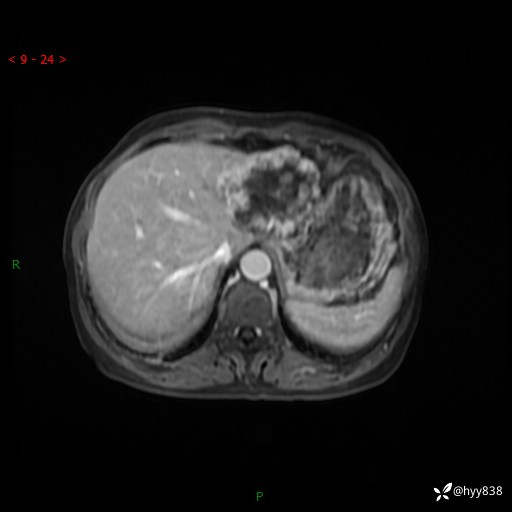

老年女性,偶然发现肝脏占位,综合各个序列,你考虑什么---结果公布

患者年龄:66岁

主诉:发现肝脏占位性病变2天

简要病史:患者2天前因“腰疼”至当地医院就诊时发现肝脏左叶占位性病变,无发热、畏寒,无皮肤黄染,无腹痛、腹泻,无恶心、呕吐、厌油等不适,今进一步诊治遂来我院就诊,门诊以“肝脏占位性病变性质待查”收入我科。 起病以来,患者精神、睡眠一般,饮食欠佳,二便正常,体力、体重无明显减轻,

辅助检查:MRI

临床诊断:肝占位

肝脏MRI平扫(同反相位)

T2WIfs+DWI

增强(动脉期+静脉期+延迟期)